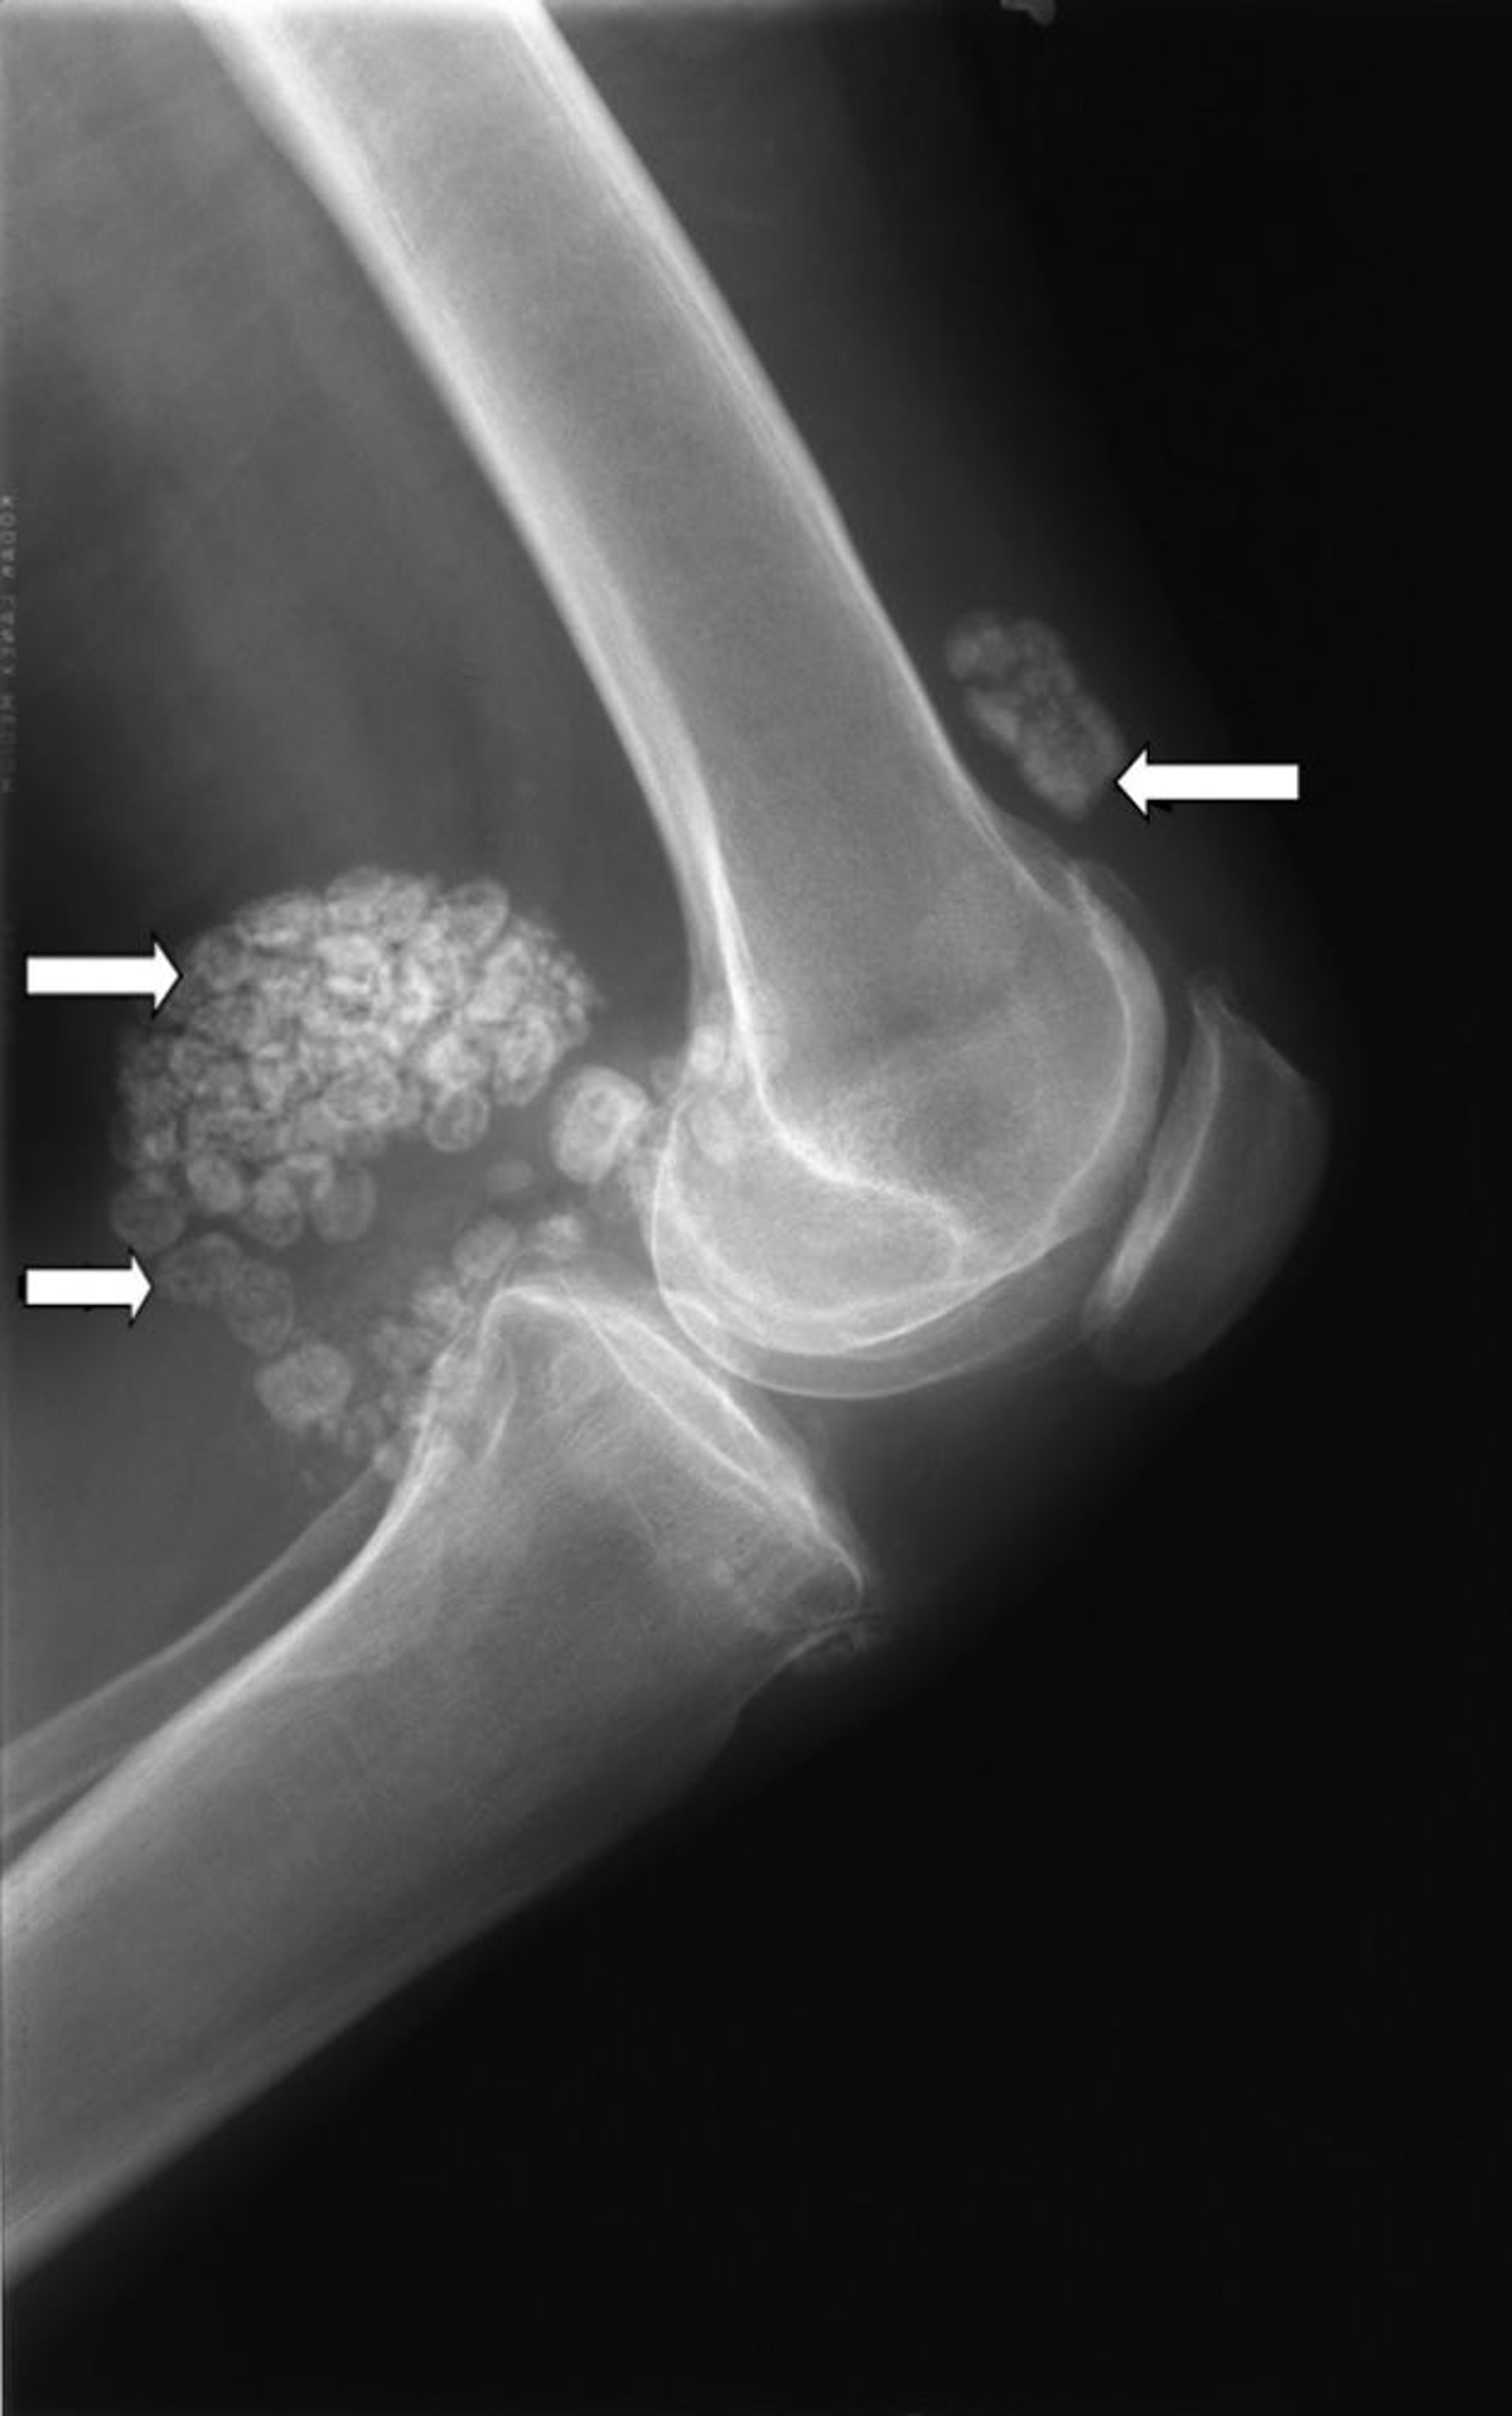

滑膜軟骨腫症

この膝のX線写真には、滑膜軟骨腫症として知られる複数の軟骨の塊が写っています(矢印)。

Image courtesy of Michael J.Joyce, MD, and Hakan Ilaslan, MD.